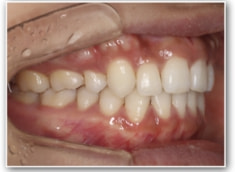

治療法:裏側の矯正(リンガルブラケット:舌側矯正)

治療後